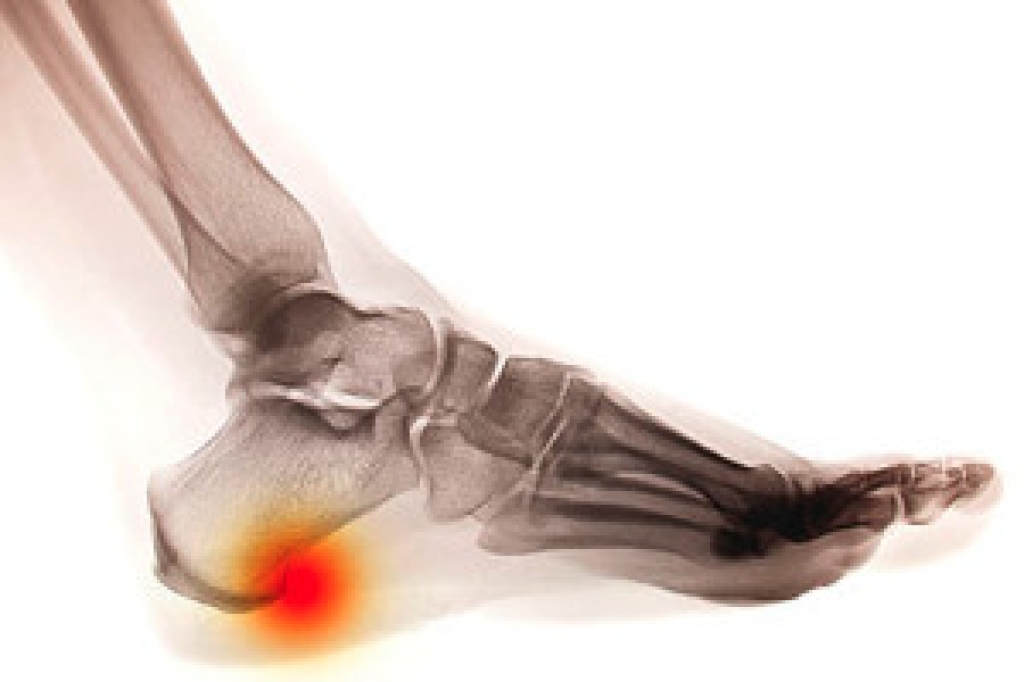

Heel pain is a frequent complaint that can interfere with daily movement and quality of life. Common causes include plantar fasciitis, which involves inflammation of the tissue along the sole, and Achilles tendonitis, which affects the tendon connecting the heel to the calf. Heel spurs, or bony growths, and stress fractures in the heel bone can also lead to persistent discomfort. Risk factors include excessive physical activity, improper footwear, obesity, and tight calf muscles. A podiatrist can identify the specific cause of heel pain through examination and imaging, then create a treatment plan involving stretching, footwear changes, orthotics, or other therapies. If you suffer from heel pain, it is strongly suggested that you consult a podiatrist for an expert diagnosis and relief strategies.

Heel pain is often associated with plantar fasciitis. The plantar fascia is a band of tissues that extends along the bottom of the foot. A rip or tear in this ligament can cause inflammation of the tissue.

Heel spurs are another cause of pain. When the tissues of the plantar fascia undergo a great deal of stress, it can lead to ligament separation from the heel bone, causing heel spurs.

Heel pain should be treated as soon as possible for immediate results. Keeping your feet in a stress-free environment will help. If you suffer from Achilles tendonitis or plantar fasciitis, applying ice will reduce the swelling. Stretching before an exercise like running will help the muscles. Using all these tips will help make heel pain a condition of the past.